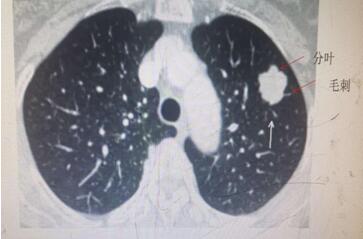

肺內(nèi)結(jié)節(jié),不容忽視,但也不必驚慌。肺部小結(jié)節(jié)并非一定就是肺癌,惡性腫瘤遠(yuǎn)少于良性病變。一般根據(jù)結(jié)節(jié)大小、形態(tài)并結(jié)合你的年齡與吸煙狀況來分析。通常以下情況肺癌的可能性大:年齡在55歲以上;有慢性肺部疾病史和家族史的患者;肺部小結(jié)節(jié)直徑>1厘米;邊緣有毛刺和分葉;內(nèi)部密度不均勻表現(xiàn)為實(shí)性結(jié)節(jié)或者混雜性結(jié)節(jié)。需要注意的是,有吸煙史的人,是肺癌的高危人群,年數(shù)乘以每天吸煙的支數(shù)>400支/年的吸煙患者患肺癌的幾率會(huì)明顯增高。